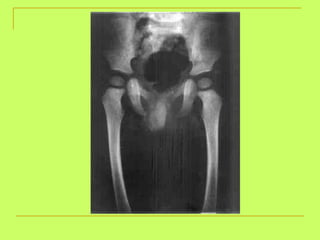

> 18 y (head of femur)<23 opened iliac crest  >23 y (iliac crest)

What is the age? <23 y (non-united iliac crest)

Age from hip bone examination: Two pubic rami of the hip  (6y) Suture at the acetabulum  (15y). Ischeal tuberosity with the ischium  (21y). Iliac crest with the ilium  (23y).

Age from hipbone examination: Two pubic rami of the hip (6y) Suture at the acetabulum (15y). Ischeal tuberosity with the ischium (21y). Iliac crest with the ilium (23y).